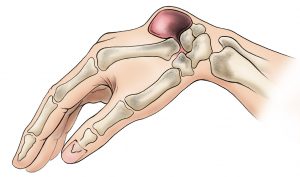

La tendinite de De Quervain est une inflammation des tendons du pouce situés sur le bord externe du poignet, plus précisément ceux du long abducteur (APL) et du court extenseur du pouce (EPB).

tendinite de De Quervain

La tendinite de De Quervain correspond à une inflammation de la gaine synoviale entourant deux tendons essentiels du pouce :

• le long abducteur du pouce (APL),

• et le court extenseur du pouce (EPB).

Ces tendons glissent dans un canal étroit situé sur le bord radial du poignet. Lorsqu’ils sont sollicités de manière excessive ou répétée, la gaine s’épaissit et frotte, provoquant une douleur aiguë et localisée.